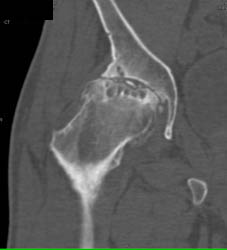

Child Fell on Foreign Body